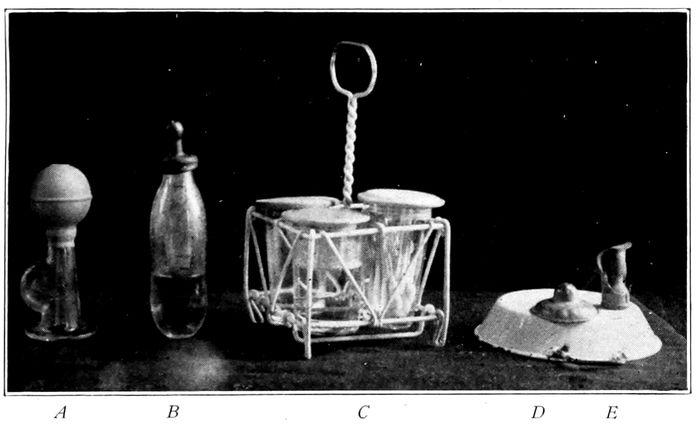

Standard breast pump; Standard nursing bottle; the breast tray; the Wansbrough lead nipple shield; the Brophy nipple for harelip and cleft palate |

271 |